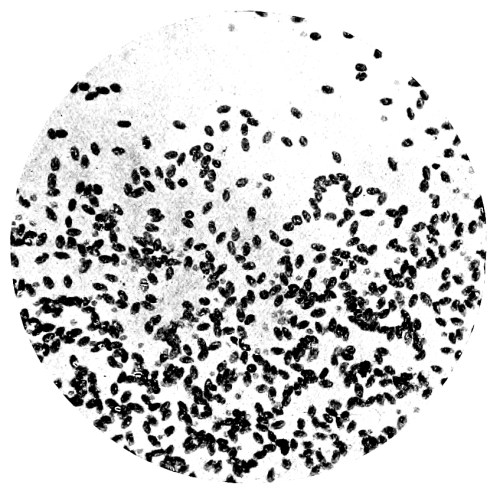

8. Measurement of Blood Corpuscles (human) 97

9. Measurement of Blood Corpuscles (sheep) 97

10. Photo-micrograph of Red Blood Corpuscles from Domestic Fowl 99

11. Photo-micrograph of Blood Corpuscles of Fish 99

12. Photo-micrograph of Blood Corpuscles from a Dried Stain of the Blood of a Cod-fish 100

13. Photo-micrograph of a Frog‘s Blood showing oval nucleated Red Corpuscles 101

14. Photo-micrograph of Crystals of Hæmin 102